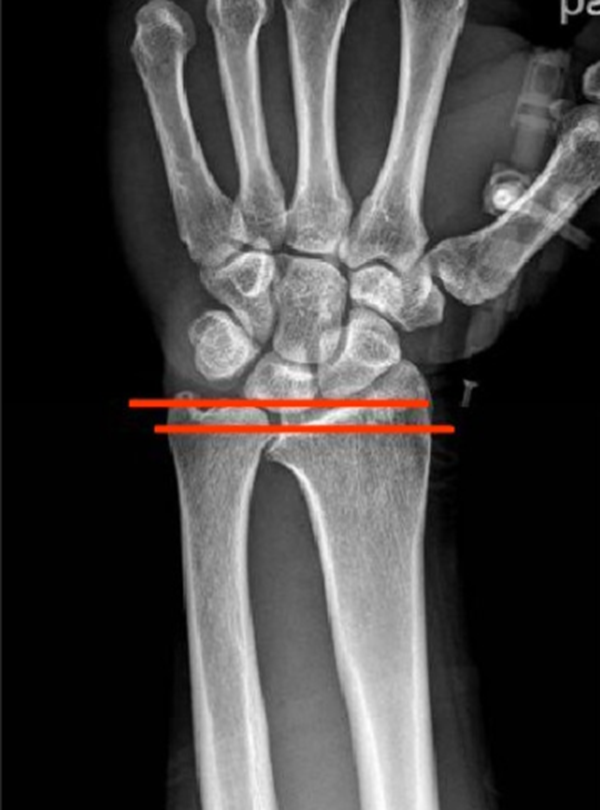

(1)X线 检查尺骨、桡骨直接位置及退化情形,通常无直接征象。

影像学检查